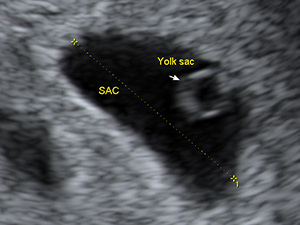

First Trimester